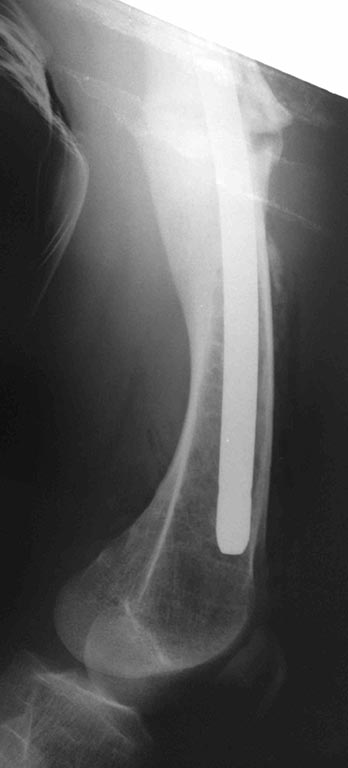

[Ortho] перелом бедра с исходной деформацией

Сегодняшние снимки из операционной, подходящей пластины не было, а

гвоздь был.